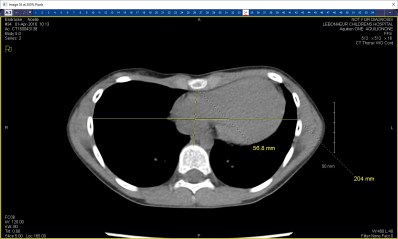

This is my daughter’s CT scan:

She has what’s called a “Haller Index” (which refers to the proportion of width vs. depth of her chest) of 3.58. A typical person’s Haller Index is 2.5, and anything over 3.25 is considered “severe” and a candidate for surgery. Notice that the heart is squished and moved out of position and how narrow it is from her backbone to her sternum.